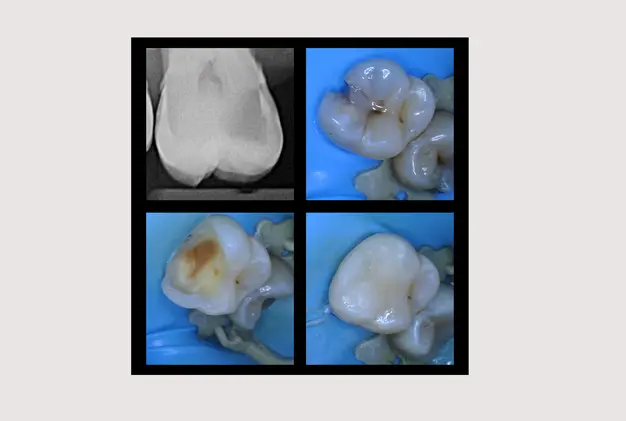

Dental fillings (Tooth Fillings) or White Fillings are restorative materials that can prevent tooth damage from worsening and restore teeth to their original appearance and shape.

We use them when natural tooth structure is damaged and decayed.

By removing this damaged part of your tooth and replacing it with a filling, you can enjoy better oral health and restore the tooth to its natural appearance and shape.